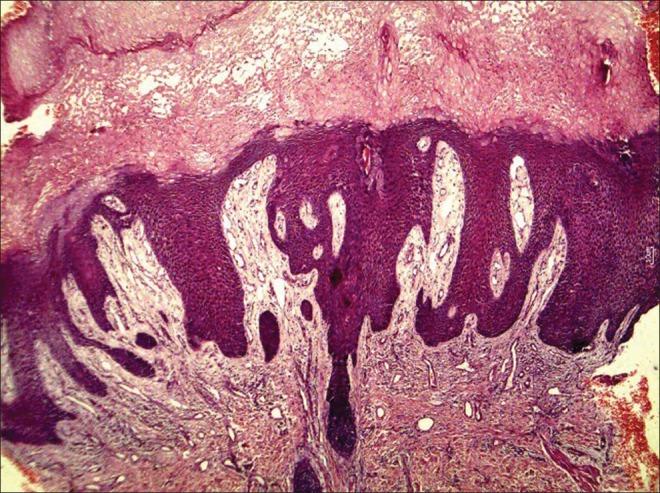

Perianal pseudoverrucous papules and nodules (PPPN) is a rare entity attributed to chronic irritation. We came across this entity in a case of spina bifida. A 14 year old girl having spina bifida at L3 presented with complaints of multiple asymptomatic whitish lesions on the inner aspect of thighs and labia majora since early childhood. She had incontinence of stool and urine since birth. Cutaneous examination revealed multiple 3-12 mm flat topped moist papules, few verrucous nodules, some of these lesions coalesced to form plaques at the perianal area extending upto the labia majora. On histology marked epidermal hyperplasia and pale keratinocytes in the epidermis was seen. This confirmed the diagnosis of PPPN. This rare condition can be mistaken with sexually transmitted diseases leading to unnecessary investigations and treatment.

肛周假性疣状丘疹和结节(PPPN)是一种罕见的因慢性刺激引起的病症。我们在一例脊柱裂病例中遇到了这种情况。一名14岁L3水平脊柱裂的女孩自幼年起就出现大腿内侧和大阴唇内侧多个无症状白色病变的主诉。她自出生以来就有大小便失禁。皮肤检查发现多个3 - 12毫米的平顶湿润丘疹、少数疣状结节,其中一些病变融合形成斑块,位于肛周区域并延伸至大阴唇。组织学检查可见表皮明显增生以及表皮内苍白的角质形成细胞。这证实了PPPN的诊断。这种罕见病症可能会被误诊为性传播疾病,从而导致不必要的检查和治疗。